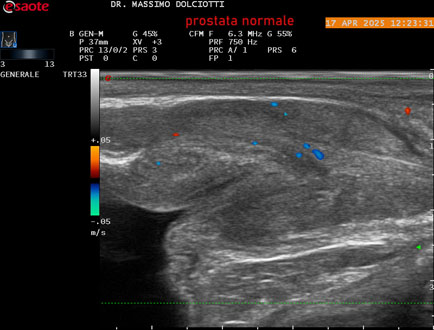

Data inserimento: 01/10/2025

Ecografia del: 17/04/2025

Strumento: Esaote MyLab Eight

Sonda: Convex Multifrequenza 1-8 MHz, Endocavitaria Multifrequenza 3-9 MHz e 3-13 MHz

Età Paziente: M 35 anni

Motivazione dell'esame: disuria.

Commento all'esame: le immagini ed il video documentano la prostata di ecostruttura regolare e morfovolumetria normale con diametro trasversale di 40 mm, diametro anteroposteriore di 21 mm e diametro longitudinale di 43 mm, con volume prostatico calcolato di 18 cc (v.n. < 20 cc), il profilo prostatico è regolare e netto, non si documentano calcificazioni intraghiandolari, la vascolarizzazione della ghiandola è normale. La vescicola seminale destra presenta diametro longitudinale di 44,4 x 7,8 mm, la vescicale seminale sinistra ha diametro longitudinale di 45,3 mm x 7,2 mm.

Conclusioni: prostata normale (normal prostate).